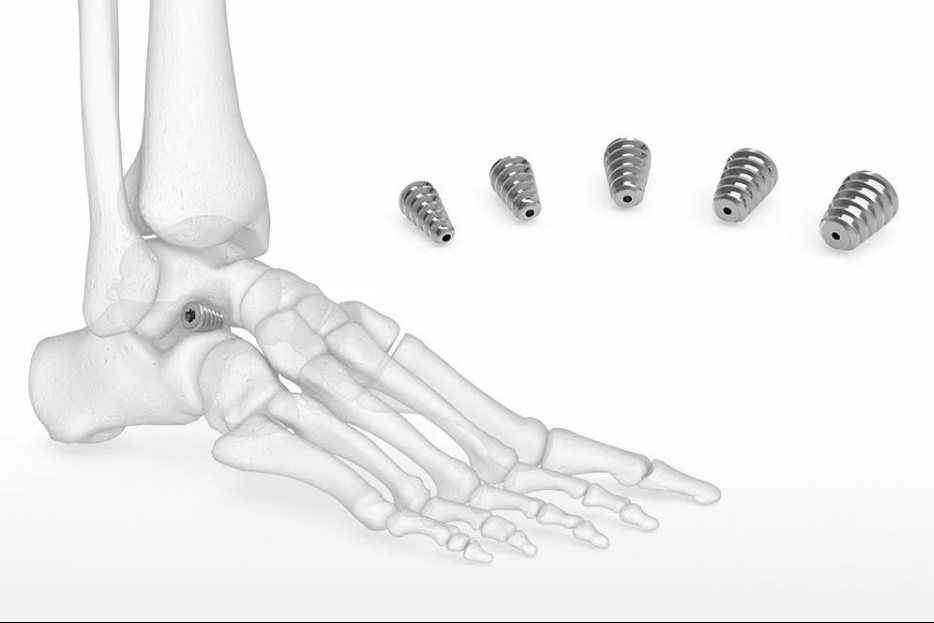

А) Простая в техническом плане. Когда при соответствующих условиях мы делаем самую простую операцию — вставляем между таранной и пяточной костями стопы «распорку» — небольшой титановый конус, который не позволяет этим костям сдвигаться относительно друг друга, и допускать коллапс стопы. Называется операция «артроэрез».

Одна эта простейшая (10 минут) манипуляция позволяет сформировать продольный свод стопы, и поддерживать этот свод на протяжении всего периода роста ребёнка. Разумеется, предупреждая дальнейшие деформации, позволяя костям формироваться и расти при правильном распределении нагрузок на скелет.

Обошлось максимально простой хирургией:

Вот такими двумя имплантами (одновременно). Прошло 7 лет, картина вот такая: